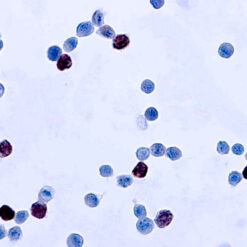

Leukocyte Common Antigen (LCA)/CD45

CD45R, also designated CD45 and PTPRC, has been identified as a transmembrane glycoprotein, broadly expressed among hematopoietic cells. Multiple isoforms of CD45R are distributed throughout the immune system according to cell type. These isoforms arise because of alternative splicing of exons 4, 5, and 6. The corresponding protein domains are characterized by the binding of monoclonal antibodies specific for CD45RA (exon 4), CD45RB (exon 5), CD45RC (exon 6) and CD45RO (exons 4 to 6 spliced out). The variation in these isoforms is localized to the extracellular domain of CD45R, while the intracellular domain is conserved. CD45R functions as a phosphor-tyrosine phosphatase. Antibody to CD45 is useful in differential diagnosis of lymphoid tumors from non-hematopoietic undifferentiated neoplasms.

| Cellular Localization | Cell membrane and Cytoplasmic |